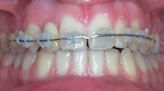

- Les appareils fixes que le patient ne peut pas retirer. Les appareils métalliques, esthétiques en céramiques (moins visibles) les appareils utilisés en technique linguale (totalement invisibles). Ils sont constitués de boîtiers ou verrous collés ou scellés sur les dents, reliés par des fils métalliques dont l’alliage, la section, la forme sont déterminés par les différentes étapes du traitement.

Il existe diverses possibilités de technique collée, externe , interne Les brackets métalliques peuvent être remplacés dans un souci d'esthétique par des éléments transparents ou de la couleur des dents.